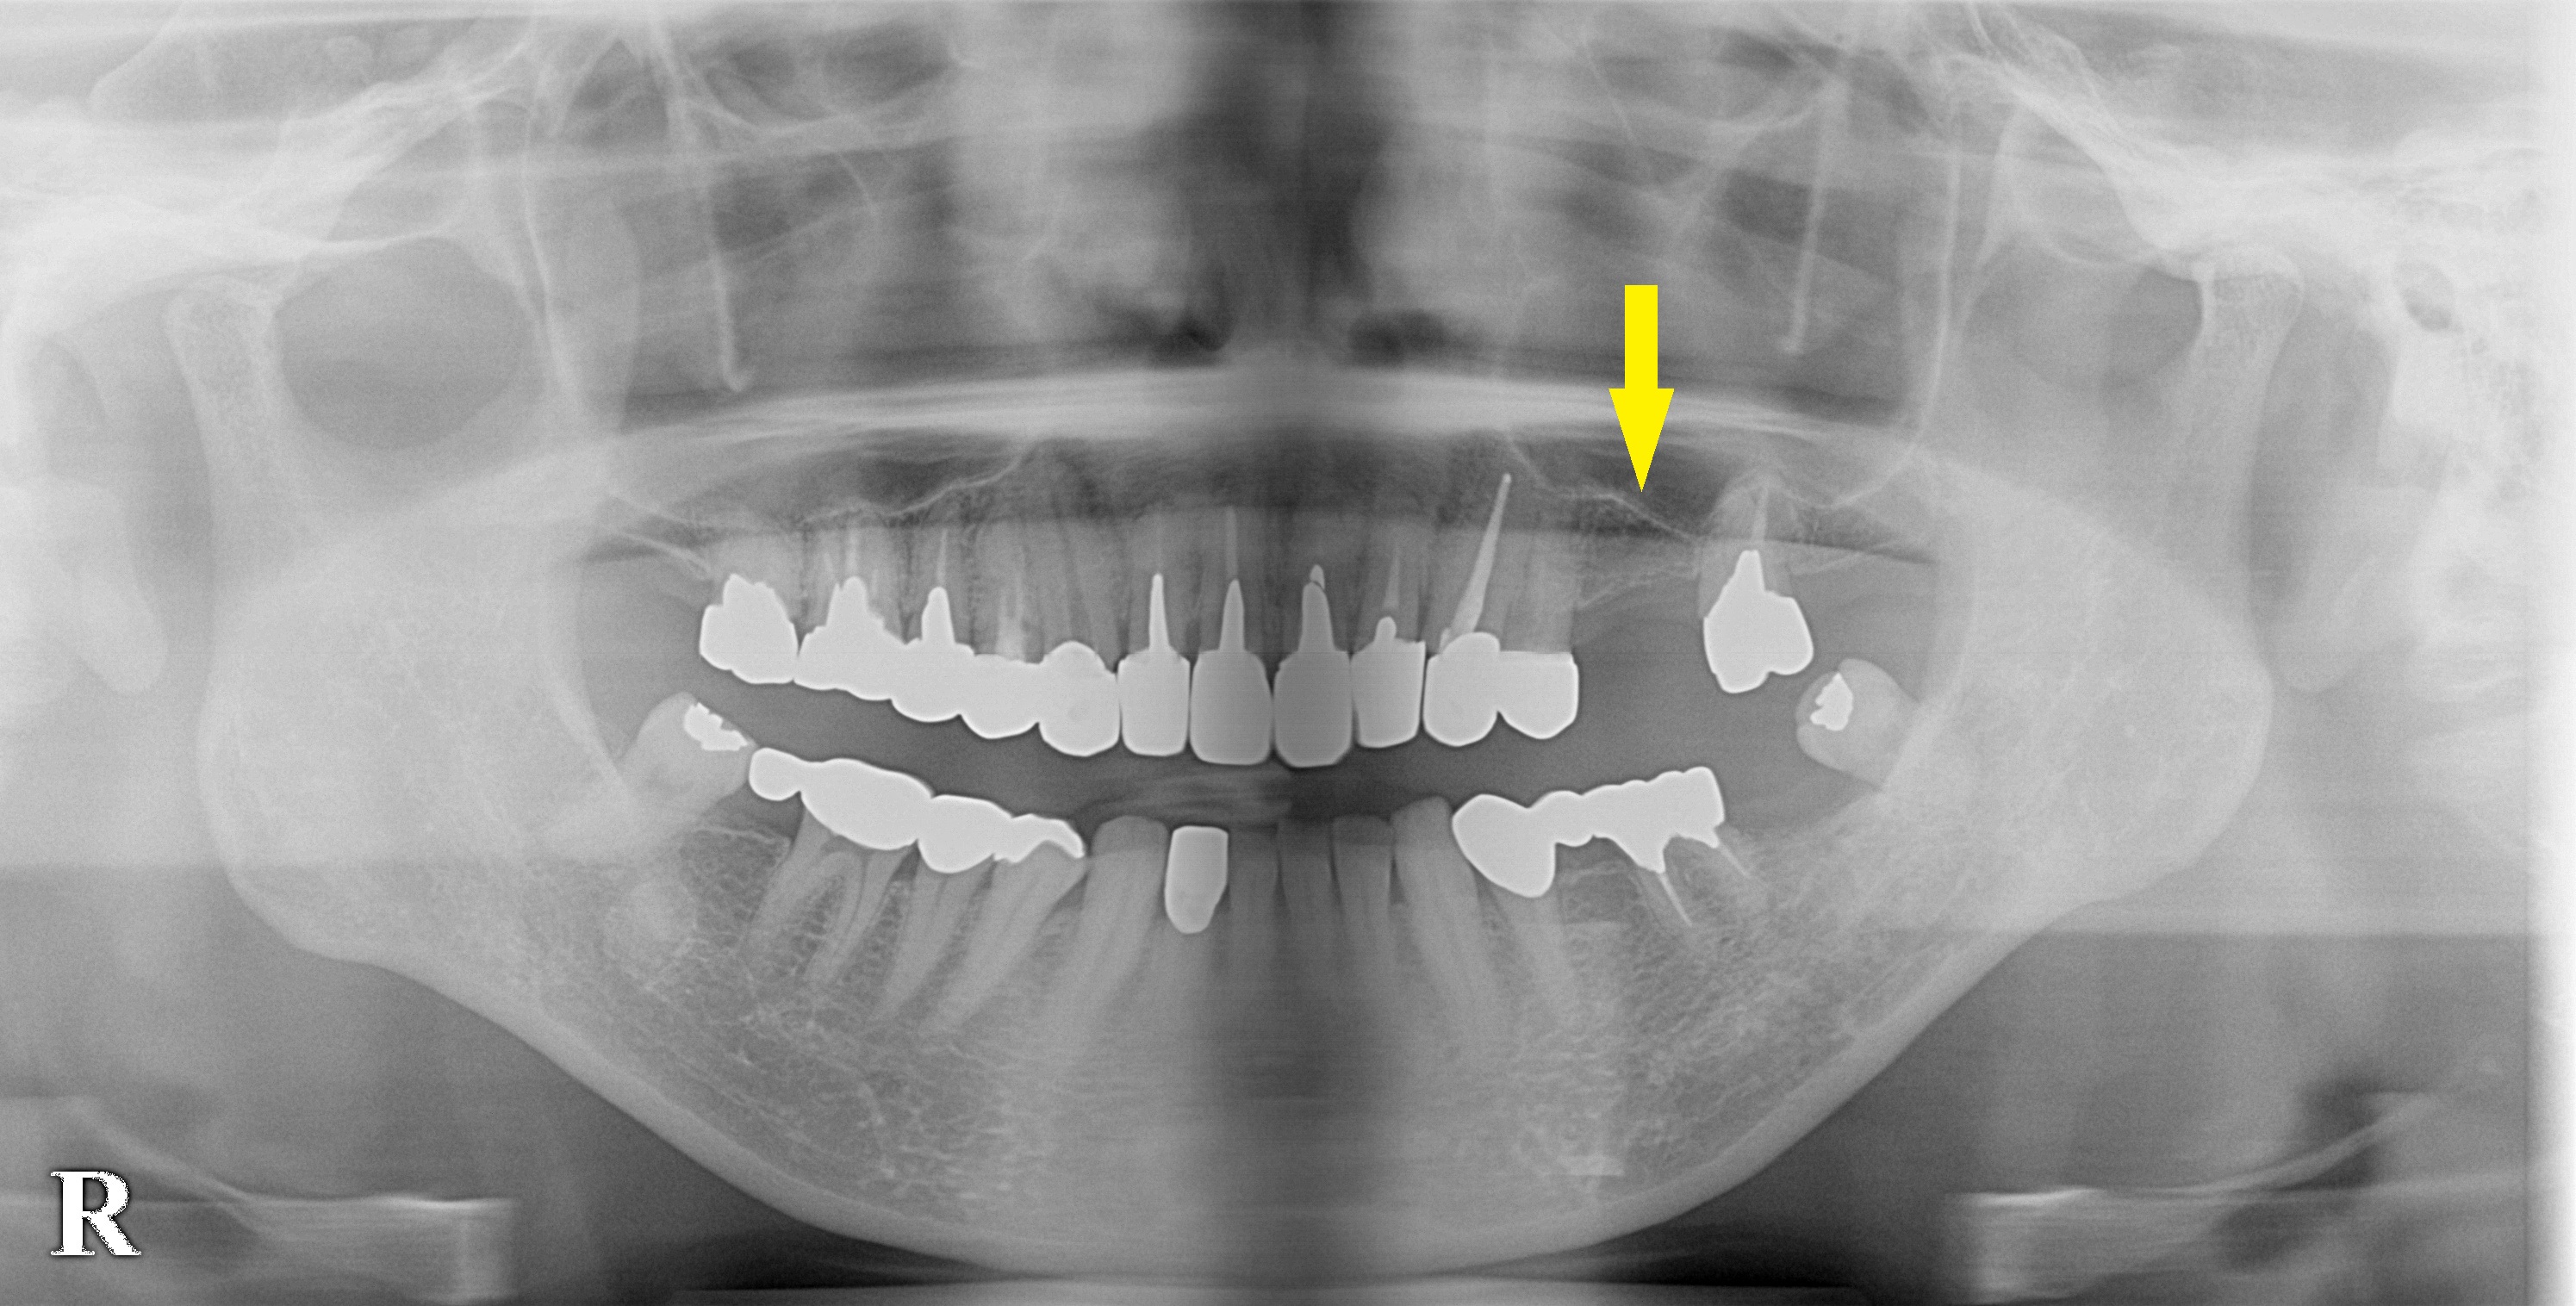

患者様は名古屋在住の50代女性。

左上顎の臼歯が抜けて、ずっと義歯で過ごされてきたそうですが、

やはり義歯では不快なことが多く、インプラント治療を希望されて相談においでになりました。

レントゲン、CTを撮影してみると、上顎の臼歯部ではよくあることですが、骨がやや薄く骨造成なしでインプラント埋入は困難でした。

ただ、ある程度の骨量はありましたので、ソケットリフトという、骨造成術を併用してインプラント埋入術を行なうことで同意をいただきました。